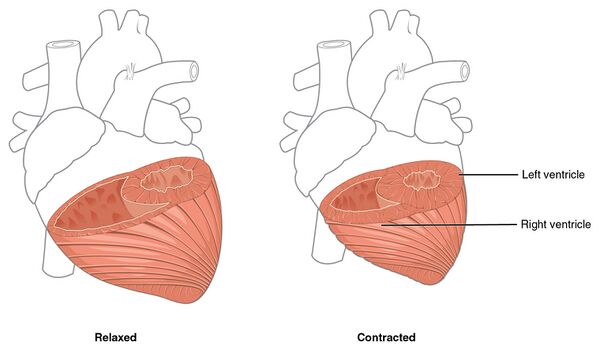

Здоровое сердце ритмично и без перерывов сжимается и разжимается. В одном цикле работы сердца различают три фазы:

- Наполненные кровью предсердия сокращаются. При этом кровь через открытые клапаны нагнетается в желудочки сердца (они в это время остаются в состоянии расслабления). Сокращение предсердий начинается с места впадения в него вен, поэтому устья их сжаты и попасть назад в вены кровь не может.

- Происходит сокращение желудочков с одновременным расслаблением предсердий. Трёхстворчатые и двустворчатые клапаны, отделяющие предсердия от желудочков, поднимаются, захлопываются и препятствуют возврату крови в предсердия, а аортальный и лёгочный клапаны открываются. Сокращение желудочков нагнетает кровь в аорту и лёгочную артерию.

- Пауза (диастола) короткий период отдыха этого органа. Во время паузы из вен кровь попадает в предсердия и частично стекает в желудочки. Когда начнётся новый цикл, оставшаяся в предсердиях кровь будет вытолкнута в желудочки — цикл повторится.

Один цикл работы сердца длится около 0,85 сек., из которых на время сокращения предсердий приходится только 0,11 сек., на время сокращения желудочков 0,32 сек., и самый длинный — период отдыха, продолжающийся 0,4 сек. Сердце взрослого человека, находящегося в покое, работает в системе около 70 циклов в минуту.